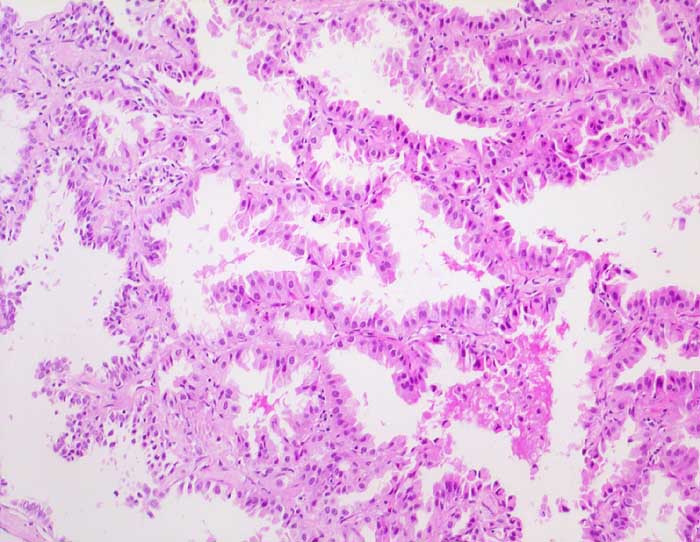

Nicht muzinöses Bronchioloalveoläres Karzinom

maligner Tumor

Lunge, Mediastinum mit Thymus

Die Alveolarsepten werden von hochprismatischen Zellen mit reichlich eosinophilem Zytoplasma ausgekleidet. Das Alveolargerüst ist erhalten und nicht wesentlich verdickt.